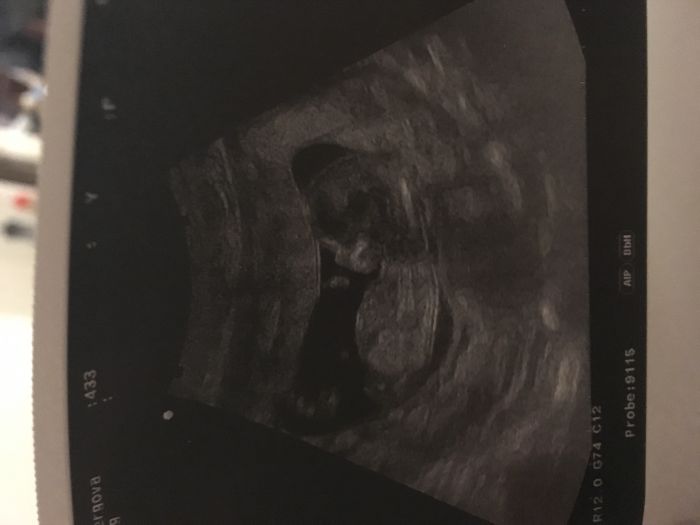

Ahoj holky, tak já už jsem taky po kontrole, odběru krve a dostala jsem průkazku :-) mrňous povyrost a je dokonce ó 2dny popredu :-) na kontrolu za měsíc , teď na ten screening do Krnova :-) snad bude vše ok... :-) ostatním holkám gratuluju k hezkým fotkám a krásným miminkům :-)

Zuzi taky krásná fotka. Až prcka uvidíš příště, bude jednou takovej